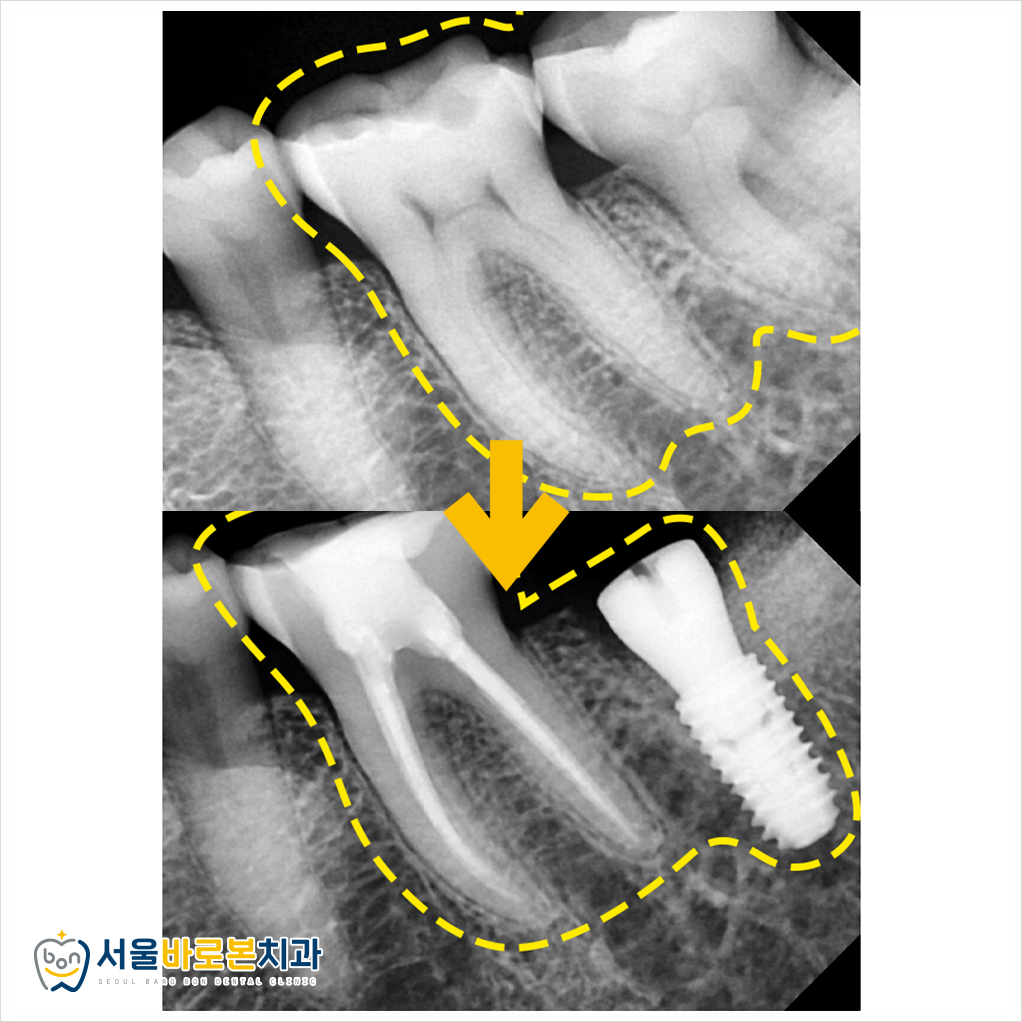

염증이 있던 부위다 보니

잇몸뼈 흡수가 조금 있었는데,

염증 조직을 깨끗하게 긁어낸 후

뼈 이식까지 함께 진행하여

무사히 임플란트 식립을 도와드렸습니다.

신경치료도 뿌리 끝까지

깔끔하게 잘 이루어졌고,

임플란트도 남은 염증 조직 없이

잘 식립된 모습을 확인하실 수 있습니다!